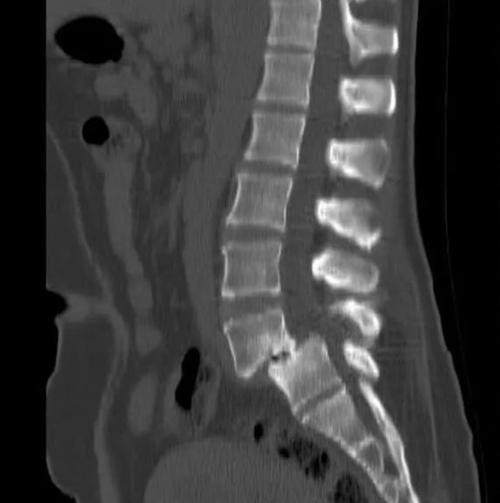

:腰4椎体向前滑脱达到了III度。

:腰4椎体向前滑脱,达到了III度。

腰4椎体向前IV度滑脱